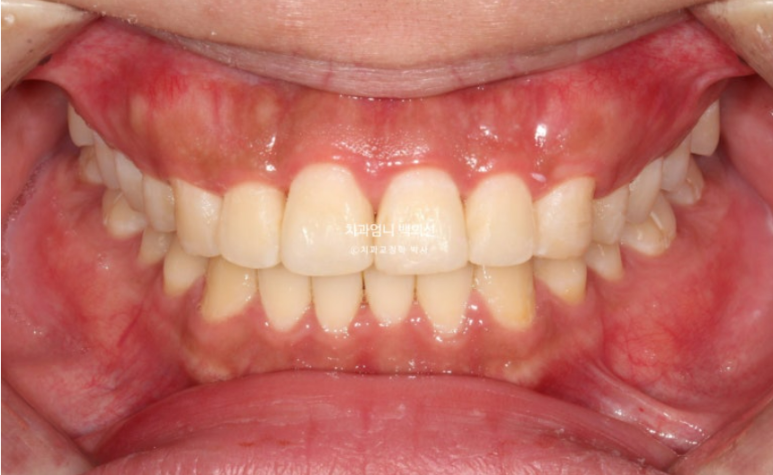

25년 6월, 5개월만에 치료를 마무리 했습니다.

25.06

문제의 앞니 끝단 모양을 조금 다듬어 마모된 부분이 티가 덜나게 해드렸습니다.

원래 좋았던 교합은 잘 유지가 되었습니다.

유지장치까지 들어간 모습입니다.